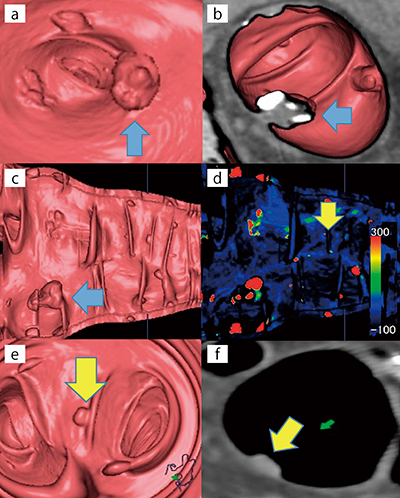

図4は,83歳,男性,悪性腫瘍の検索を目的に施行した症例である。肛門より13.1cmのS状結腸に,13.1mm×10.5mm,CT値24.9HUの腫瘍性病変がVEにて確認できる(図4 a)。腫瘍部分は表面不整の隆起性病変と認識できるが,VE+MPR画像による観察で病変+残渣であることが明瞭である(図4 b)。また,腫瘍周囲には5mm前後の小結節が散在するが(図4 c),MIP表示でCT値が300HU前後を示している結節はタギングされた残渣であると証明できる(図4 d)。散見される小結節の中に,CT値38HU,6.2mm×6.0mmのIs病変が確認できる(図4 d〜f)。このような症例においては,VGPとMIP表示の併用で解析作業の効率化を図ることができる。VGPの活用で病変と残渣の存在を分別し,証明できた一例である。

図4 仮想大腸展開画像:VGP

a:VE,表面不整の隆起性病変(↑)

b:VE+MPR画像

c:VGP

d:VGPのカラーMIP表示(CT値:赤300HU〜黒−100HU),残渣の中のIs病変(↓)

e,f:d(↓)のVEとMPRアキシャル画像